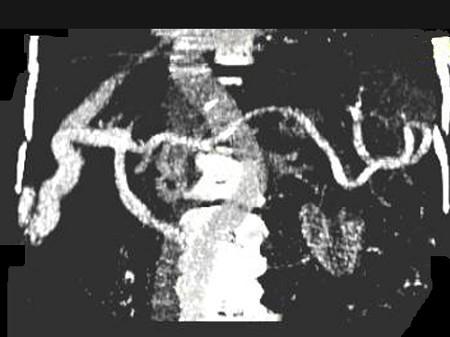

问题 女,70岁,发现乙型肝炎10年,3年前CT诊断为肝硬化,CT检查见图,最可能的诊断是 ( )

选项 A.肝癌 B.肝硬化、肝血管瘤 C.肝硬化、门脉瘤样扩张 D.肝门脉畸形 E.肝转移瘤、门脉扩张

答案 C